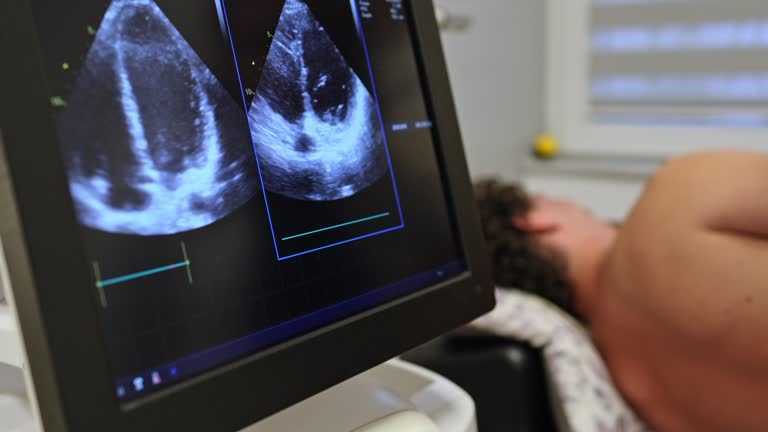

심장초음파 검사는 심장의 구조와 기능을 실시간으로 관찰하는 비침습적 진단검사로, 심장질환의 조기 발견과 정확한 평가를 위해 현대 의학에서 매우 중요한 역할을 하고 있습니다. 초음파는 인체에 무해한 고주파 음파로, 이 음파가 심장에 닿았다가 반사되어 돌아오는 파동을 영상으로 변환함으로써 심장의 크기, 형태, 운동, 혈류 흐름 등을 자세히 분석할 수 있습니다. 방사선 노출이 없고 통증이 거의 없어 임산부나 어린이, 고령자에게도 안전하게 시행할 수 있습니다. 이 검사는 심장의 기능적 상태뿐 아니라 구조적 이상까지 동시에 파악할 수 있어 심부전, 판막질환, 심근경색, 선천성 심장질환의 진단과 치료 경과 관찰에 필수적으로 사용됩니다.

심장초음파(심초음파, Echocardiography)는 심장 내부의 움직임과 혈류 상태를 영상으로 구현하는 검사입니다. 초음파 탐촉자(Probe)를 환자의 흉부에 대면, 고주파 음파가 심장으로 전달됩니다. 이 음파가 심장의 조직, 혈액, 판막 등에 부딪혀 반사되는 신호를 수집해 컴퓨터가 실시간으로 해석하고 영상을 형성합니다. 이렇게 만들어진 영상은 심장의 각 부위가 얼마나 잘 수축하고 이완하는지, 판막이 정상적으로 열리고 닫히는지, 심근의 두께나 움직임이 고르지 않은 부분이 있는지를 정밀하게 보여줍니다. 특히 도플러 초음파(Doppler Echocardiography) 기술을 통해 혈류의 방향과 속도를 색상으로 시각화함으로써, 혈액이 판막을 통해 역류하거나 협착된 부위를 통과할 때의 압력 차이와 흐름 이상을 정량적으로 평가할 수 있습니다. 심장초음파 검사는 단순히 영상을 보는 수준을 넘어, 심장의 생리적 상태를 정량화하여 수치로 분석하는 검사입니다. 심장의 각 부위별 두께, 심실의 크기, 판막 개폐 속도, 혈류 속도, 심장 내 압력 등의 다양한 지표가 측정되며, 이를 통해 의사는 심장의 기능적 이상을 세밀하게 파악할 수 있습니다. 예를 들어, 좌심실 구혈률(Ejection Fraction, EF)은 심장이 한 번 수축할 때 내보내는 혈액의 비율을 나타내는 수치로, 이 값이 55~70%면 정상으로 평가됩니다. EF가 40% 이하로 떨어지면 심부전이 의심되며, 치료 방향을 설정하는 데 매우 중요한 지표가 됩니다.